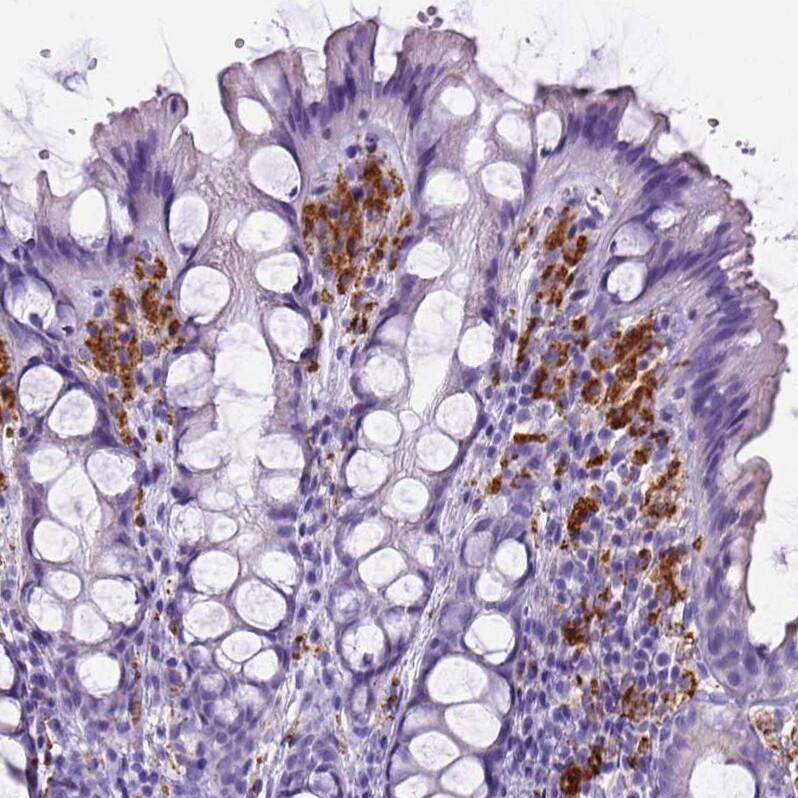

Staining of human colon shows strong cytoplasmic positivity in lymphoid cells.